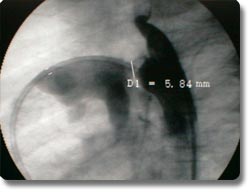

动脉导管未闭、房间隔缺损为先天性心脏发育缺陷,分别形成主动脉、肺动脉间及左右心房间的异常通道,传统治疗方式为外科开胸手术治疗。我科与国外同步开展了非手术经皮动脉导管封堵术及房间隔封堵术,用介入治疗方式矫正异常通道,手术时间30分钟左右,术后2天病员即可康复出院,疗效与外科开胸手术相同。